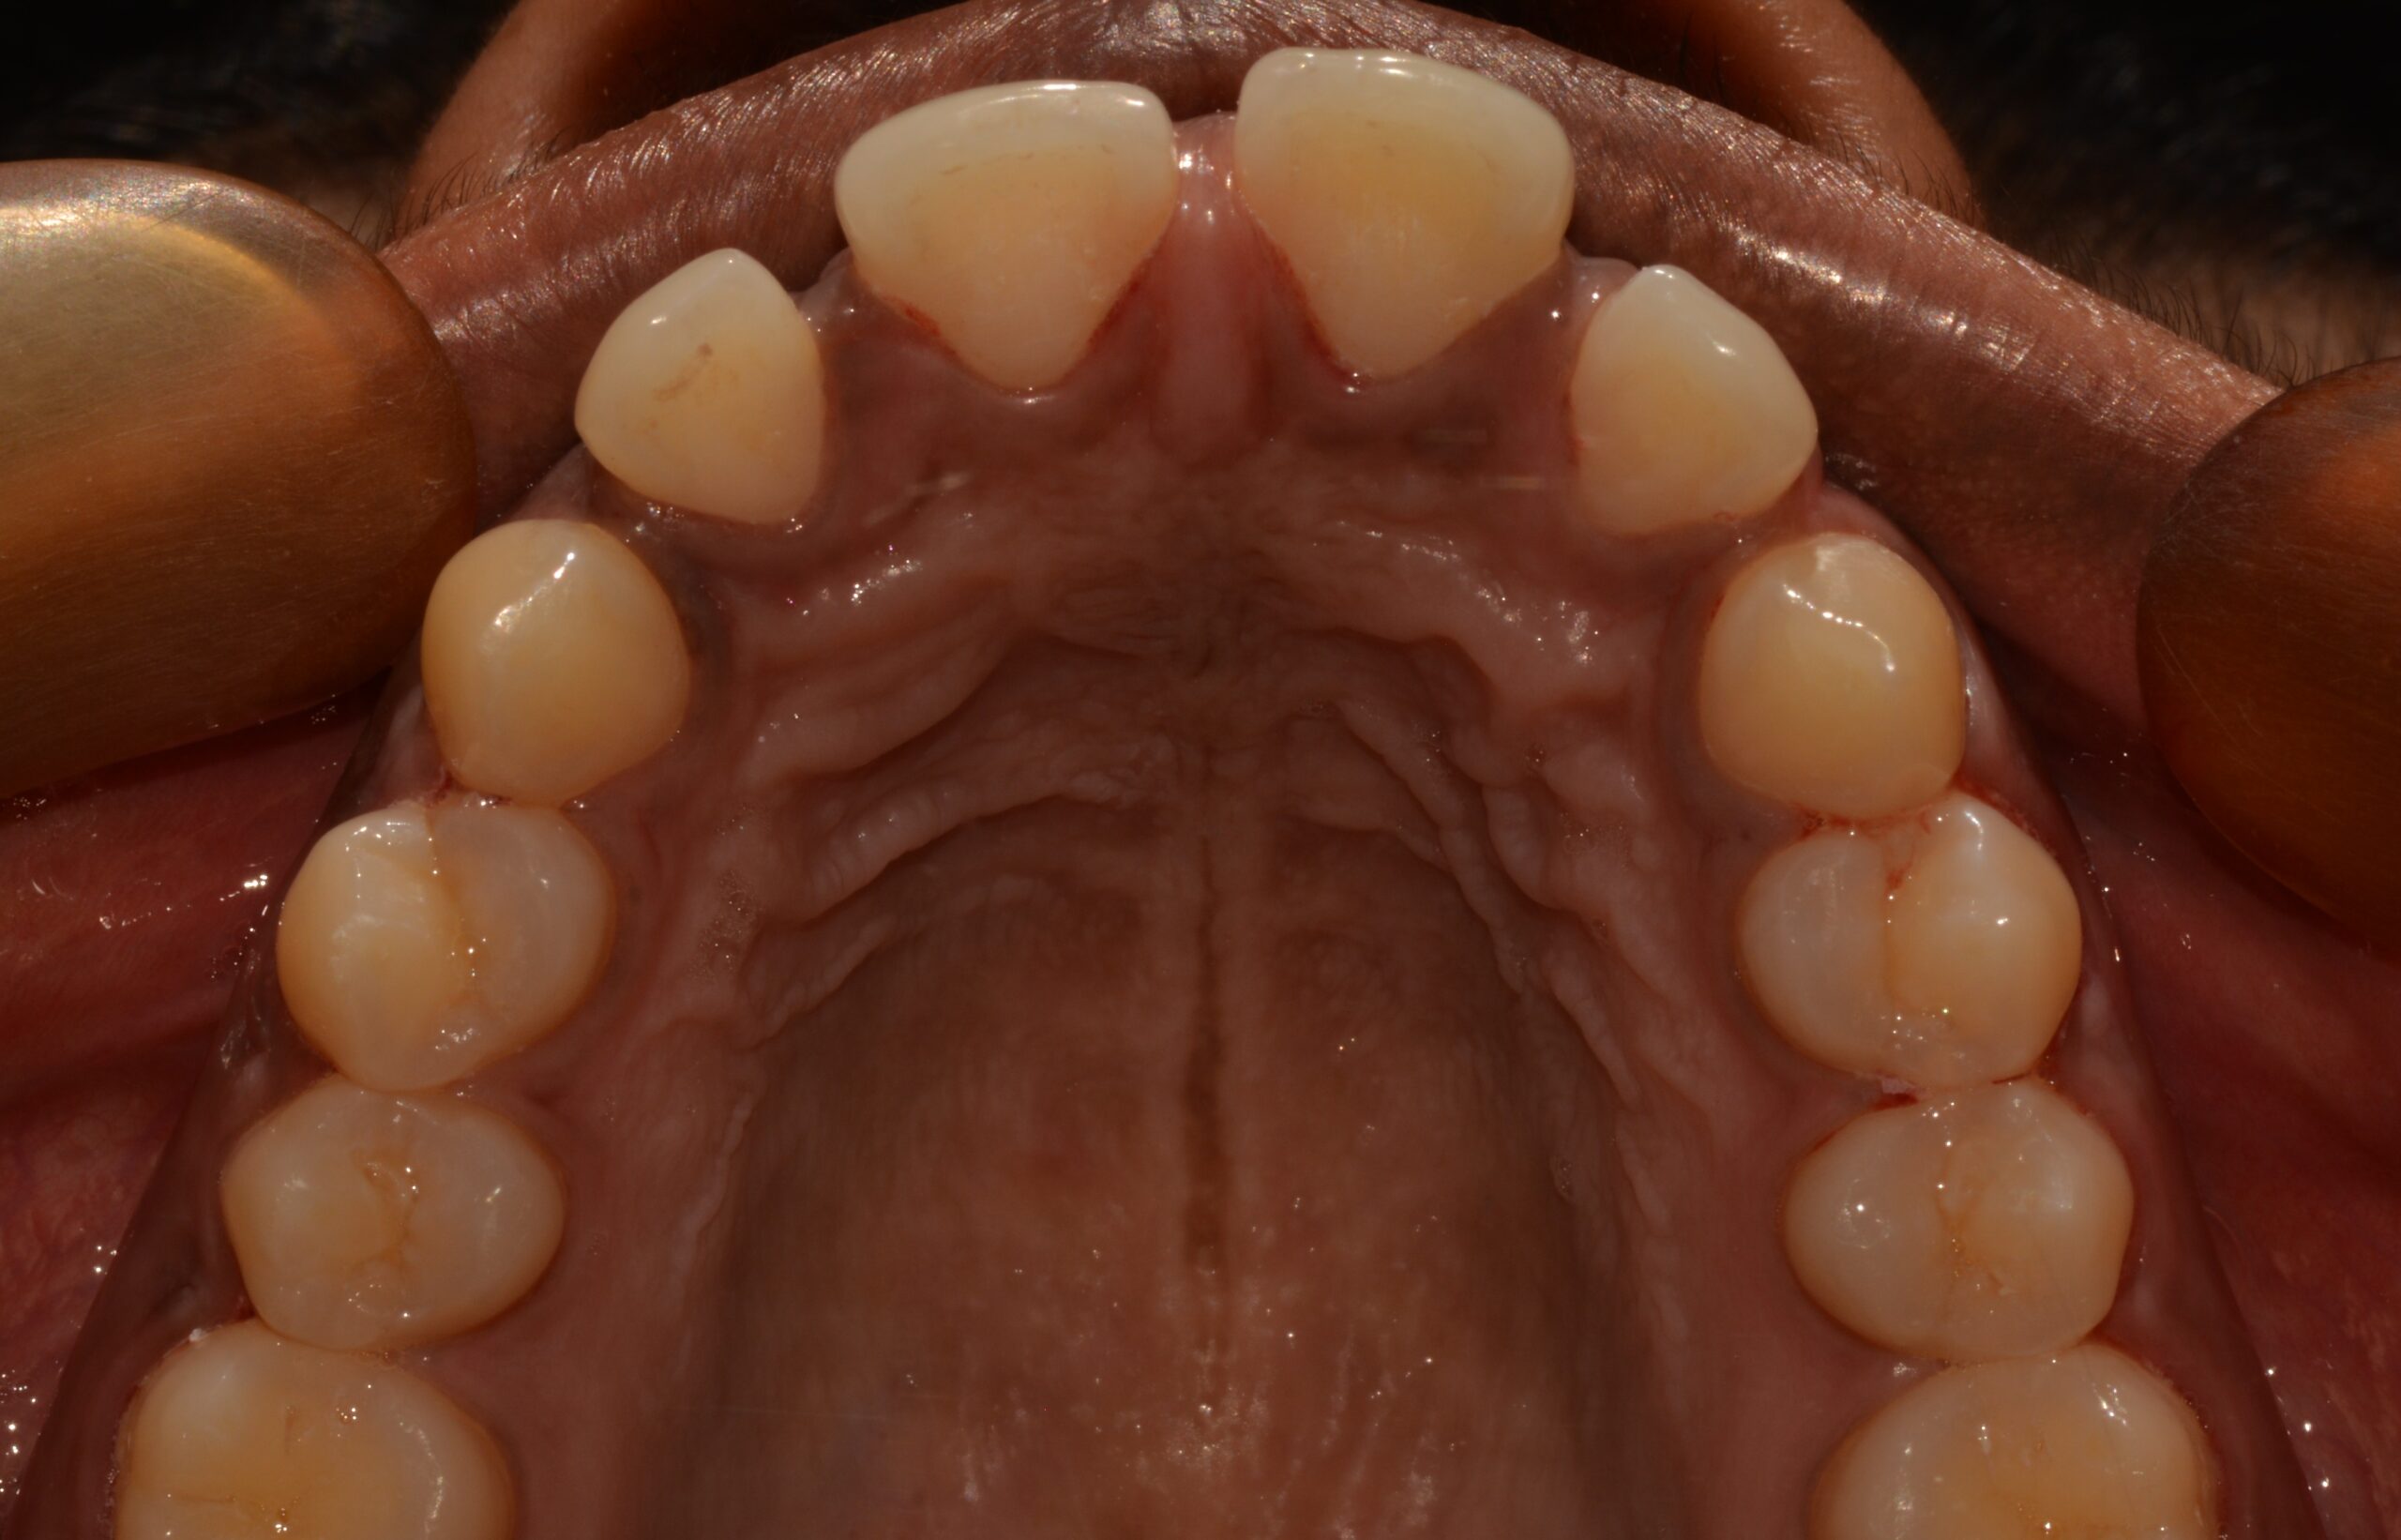

Before

After